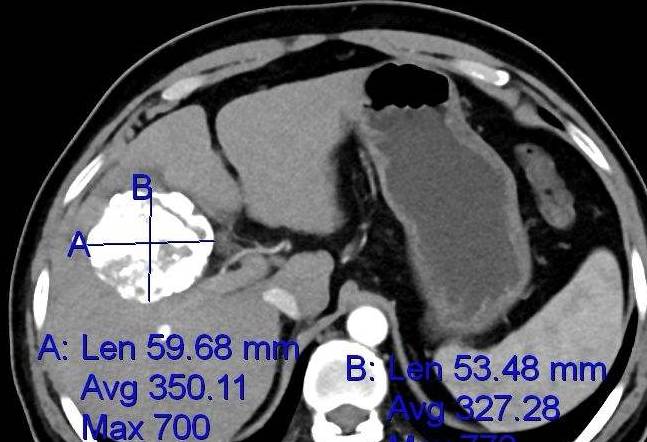

李女士做了肝CT后 , 医生发现肝脏内有一个较大肿瘤 , 确诊肝癌 。 还好发现的时间早 , 还有手术的机会 , 但李女士很是不解 , 这些红点和肝癌有什么关系呢?